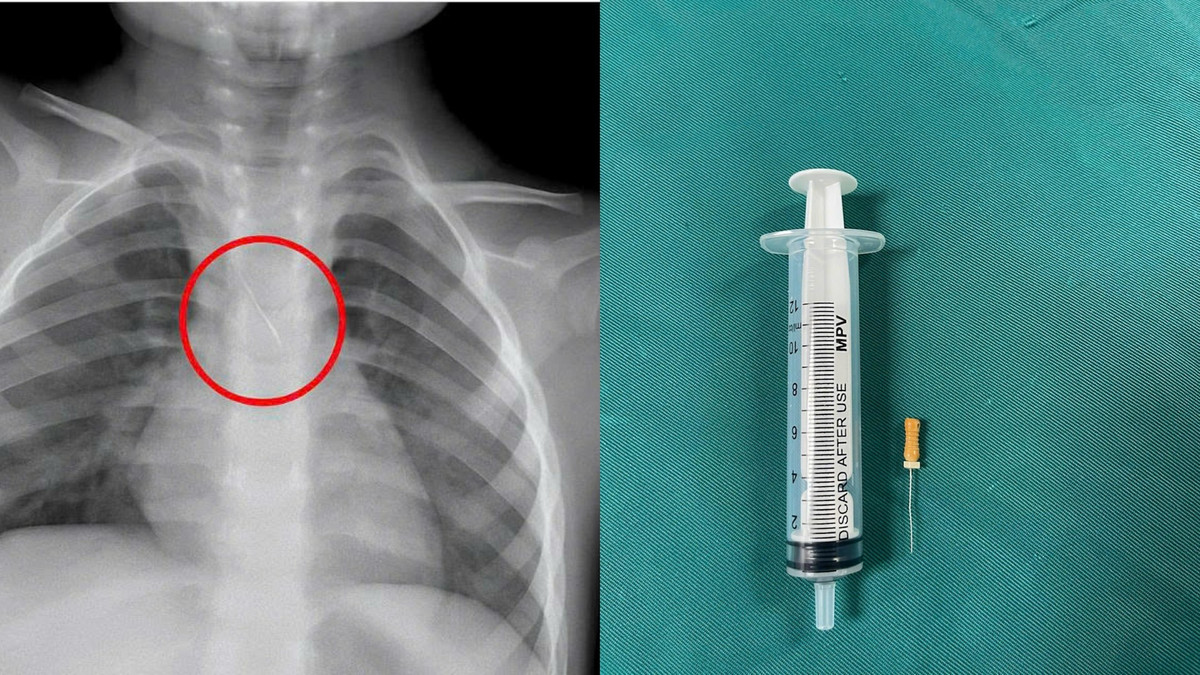

Trước đó, bệnh nhi N.Q.T.Đ. (3 tuổi, trú tại xã Cửa Việt) nhập viện trong tình trạng ho nhiều, ho sặc. Kết quả chẩn đoán hình ảnh cho thấy, bệnh nhi bị sặc kim chọc tủy vào đường thở.

Qua thăm khám và chụp phim, các bác sĩ xác định bé bị sặc kim chọc tủy dài khoảng 22mm, vị trí mắc tại góc carina, nơi chia đôi khí quản.

Dị vật này dài khoảng 22mm, nằm ở góc carina (nơi vùng chia đôi khí quản), một đầu nhọn cắm vào 1/3 dưới khí quản, một đầu tròn nằm trong phế quản gốc trái.

Các bác sĩ đánh giá, đây là trường hợp cấp cứu vô cùng nguy hiểm. Các y, bác sĩ của bệnh viện đã hội chẩn liên khoa và tiến hành nội soi phế quản cấp cứu. Sau khoảng 15 phút, các bác sĩ đã gắp thành công dị vật ra ngoài. Các triệu chứng trước đó của bệnh nhi đã được cải thiện. Hiện, sức khỏe của bệnh nhi đã ổn định và được theo dõi trong vòng 48 giờ.

Dị vật trong đường thở của bệnh nhi. Ảnh BV